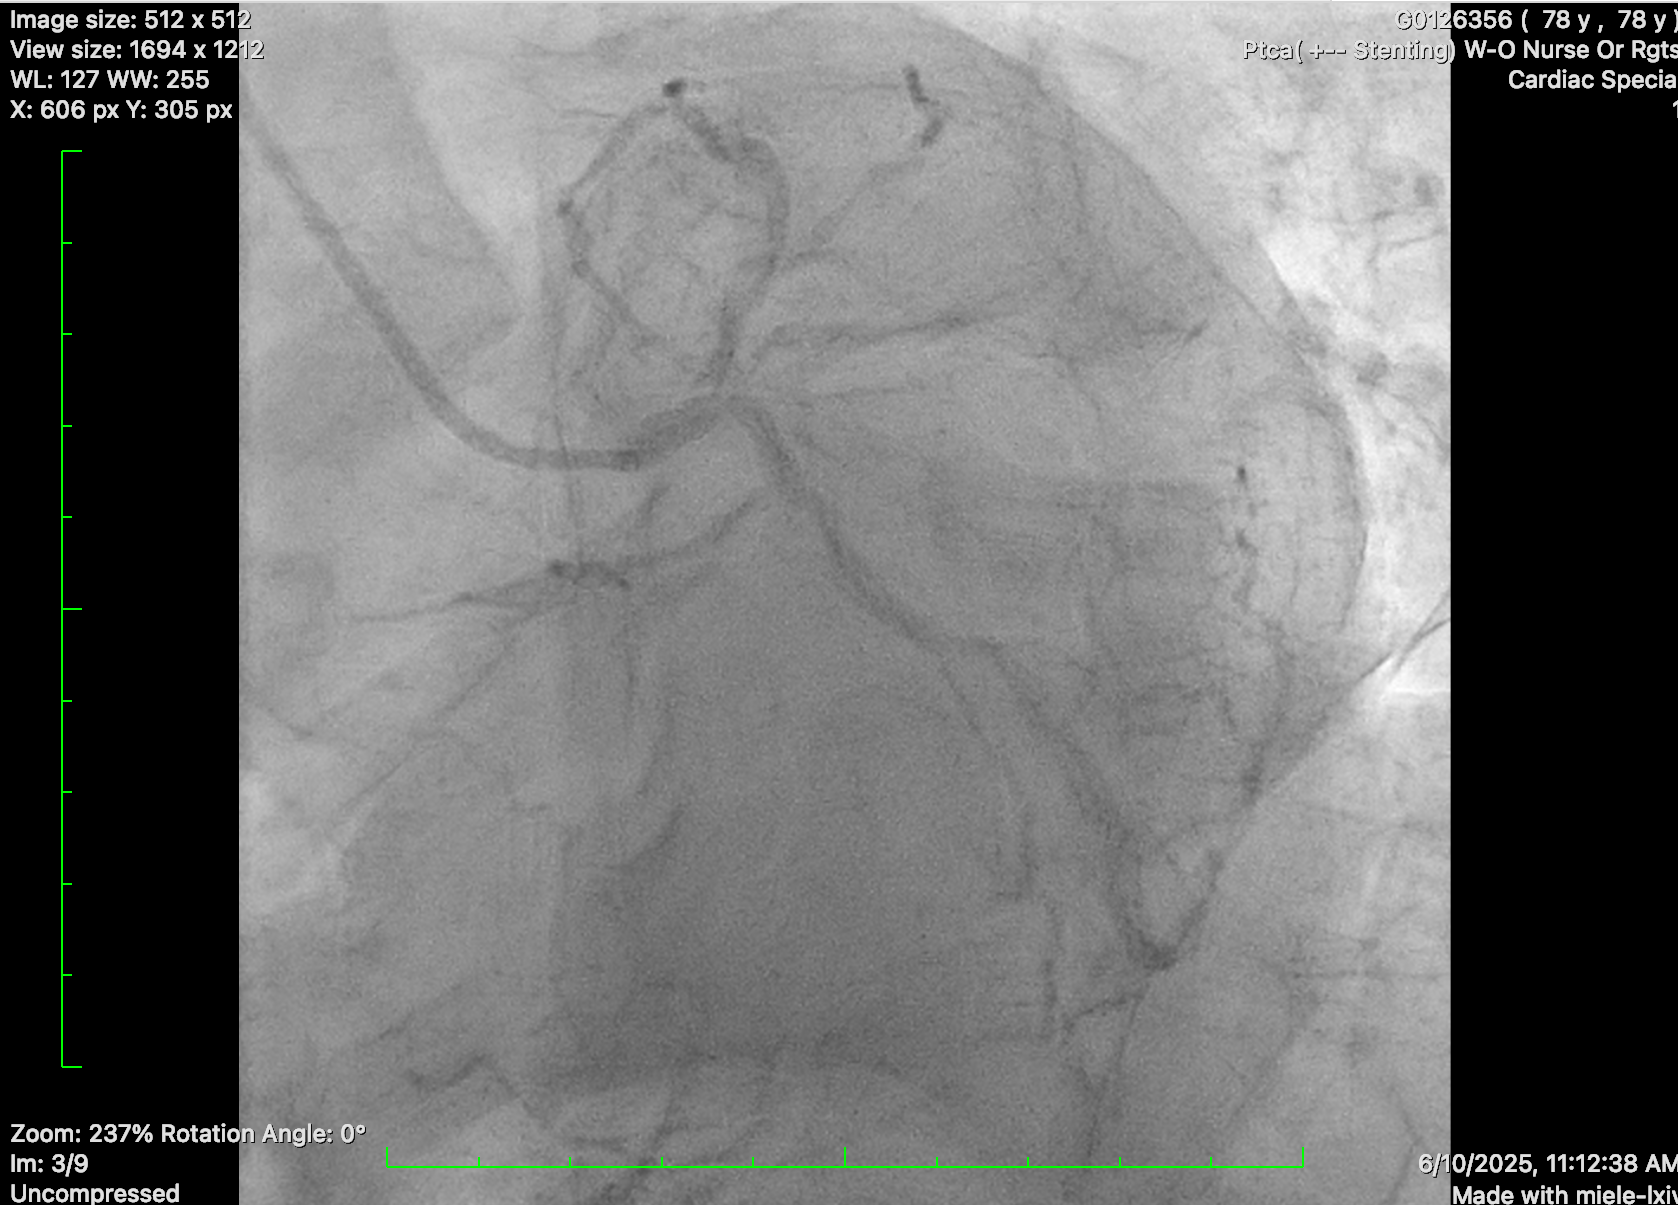

Diagnostic coronary angiogram was performed, showing distal left main disease and ostial LAD subtotal occlusion with antegrade flow, diffuse severe disease over proximal to mid LAD. Mid-LCx showed severe stenosis. RCA was dominant, with mRCA severe disease followed by subtotal occlusion with antegrade collateral to distal RCA and retrograde collateral to septal branches of LAD and diffuse severe disease at PL branch.